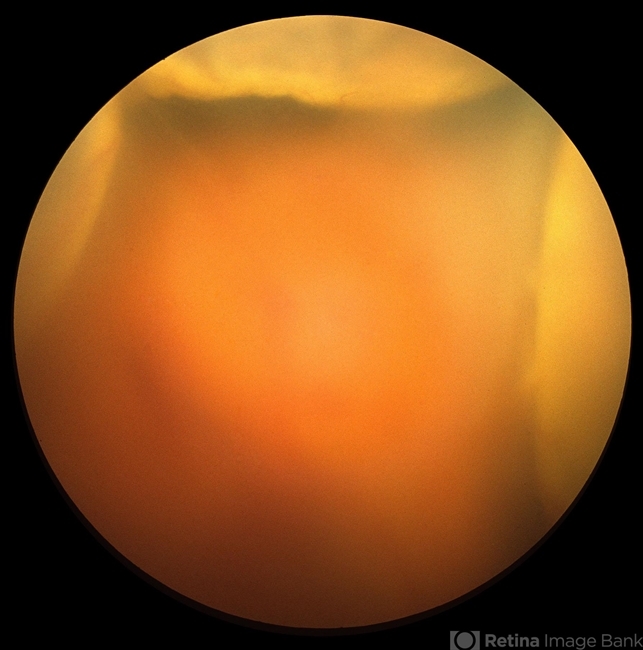

- choroidal detachment

- Choroidal detachment.